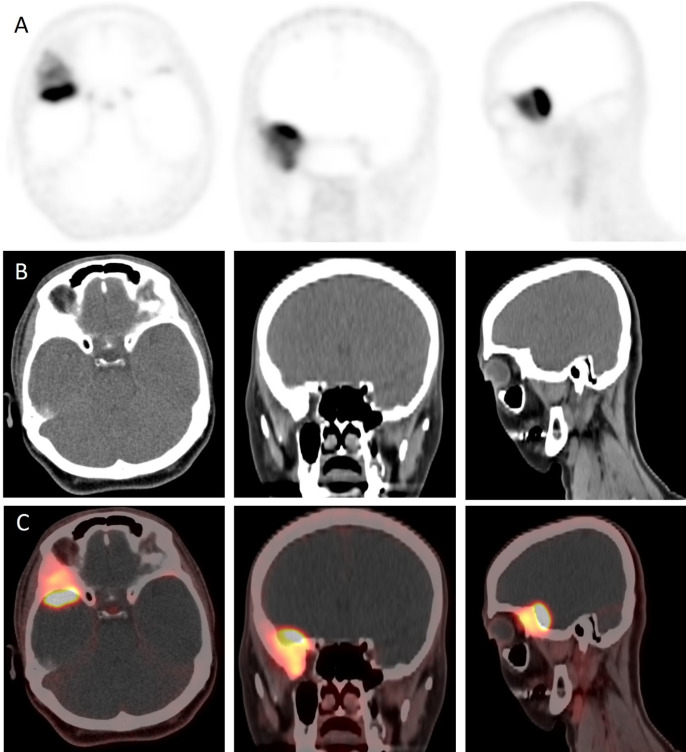

Meningiomas express the somatostatin receptor (SSTR). The utilization of SSTR ligands, specifically Gallium-68 (68Ga) isotope, a radioactive isotope (68Ga)-DOTA-labeled peptides, has demonstrated exceptional diagnostic precision for the detection of meningiomas, primarily due to the absence of normal brain and bone activity. We report a case of a 48-year-old woman with sphenoid wing meningioma who underwent 68Ga-DOTA TOC positron emission tomography (PET) for tumor delineation. 68Ga-DOTA TOC PET shows SSTR-avid meningioma in the right sphenoid/anterior temporal region with significant hyperostosis with high expression of SSTR in the bone. 68Ga-DOTA TOC uptake in the hyperostosis signifies bone infiltration rather than reactive changes. 68Ga-DOTA PET provides a better assessment of osseous involvement and provides additional information in terms of meningioma extent and planning for further management.